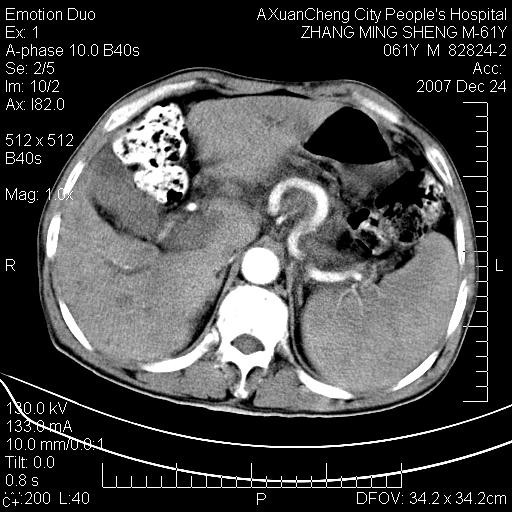

标题: CT11031:M61Y,胰腺占位

大家侃侃门静脉和胆管系统怎么回事,肝内转移?

2,肝内多发结节状低密度占位,伴门脉及肠系膜上v栓子形成.考虑a;门脉及肠系膜上v血栓后肝改变.b;弥漫型肝癌伴门脉及肠系膜癌栓.

肝硬化,门脉高压,脾肿大;弥漫性肝癌,肝内、门脉、腹膜后淋巴结转移,肝内外胆管扩张,胰头区占位,建议mr检查

胰腺癌伴肝内转移;门脉、肠系膜上v癌栓形成。

考虑为:胰腺癌伴肝脏转移、腹膜后淋巴结转移,门静脉及肠系膜上静脉瘤栓形成。

胰体尾癌伴肝内转移,门静脉及肠系膜上静脉瘤栓形成.